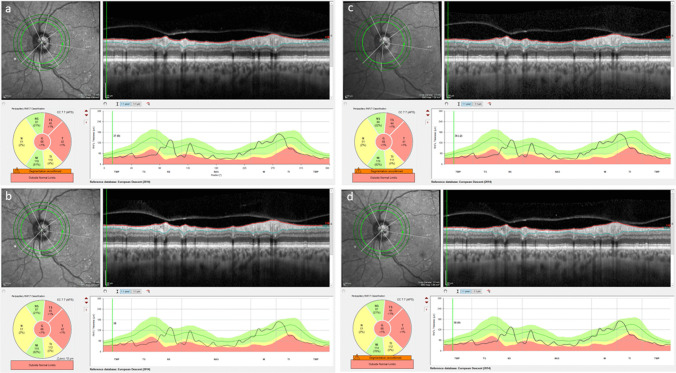

Results: Seventy eyes from 70 patients underwent surgery and completed follow-up. Forty-one patients had diabetic retinopathy and 29 had glaucoma. There was no difference in any of the recorded surgical metrics including cumulative dissipated energy (CDE) between the two randomization groups (mean CDE 6.5 versus 6.1 percent seconds in the HIGH and LOW groups respectively, p = 0.68). There were no patients in either group with posterior capsule rupture or other intraoperative complications. There was no significant difference in the number of patients with raised intraocular pressure (IOP) on day 1. Seven (21.2%) patients in the LOW and 5 (13.3%) in the HIGH group had slit lamp detectable corneal oedema on day 1, which had all resolved by day 21. There were no between group differences for visual acuity, IOP, corneal thickness, and any of the optical coherence tomography (OCT) acquired measures at any of the time points. The foveal avascular zone perimeter and area were significantly smaller on day 21 than at baseline in the HIGH group as compared to the LOW group (P = 0.03 and 0.04 respectively), with a corresponding increase in the superficial vascular plexus density (p = 0.04).